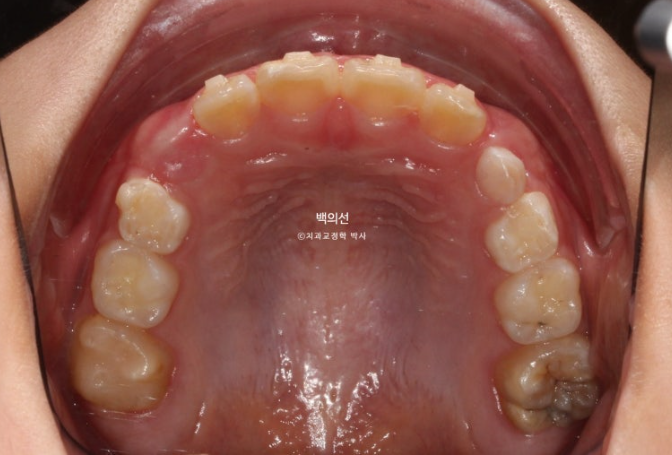

그래서 23년 11월 다시 내원하여 앞니 4개가 모두 나온 것을 확인하고 정밀진단을 했습니다.

앞니 중심선이 맞지 않고

엑스레이에서 아래턱의 골격적 비대칭으로 진단이 되었습니다.

23.12

이날 공간은 별로 부족하지 않습니다.